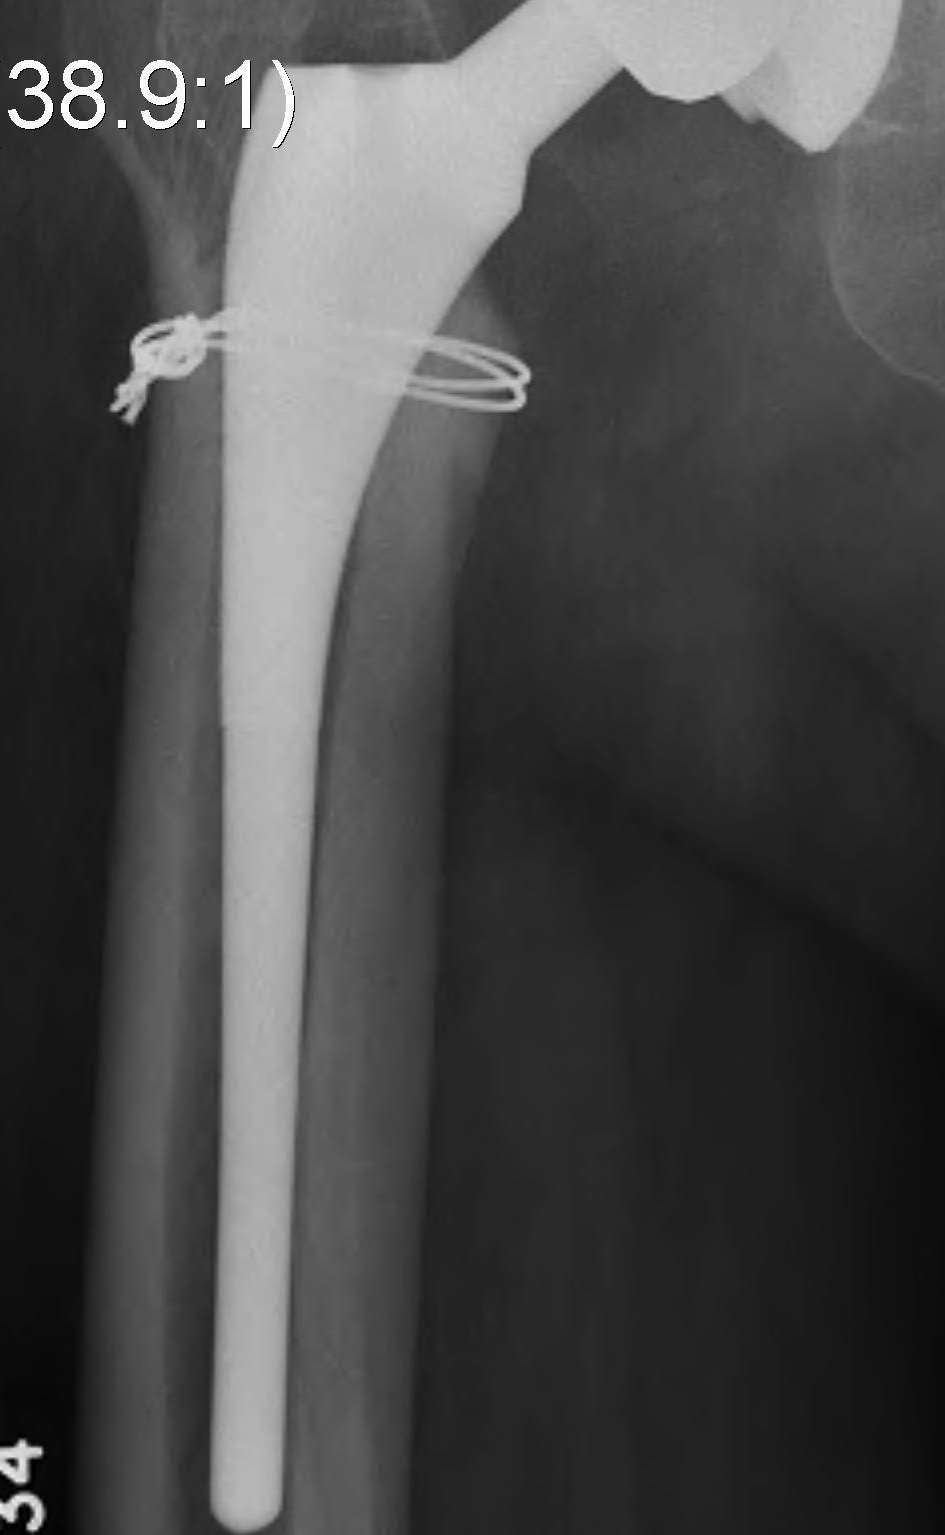

Implant insertion

Management

Cerclage wires

+/- bypass fracture with longer stem

+/- plate